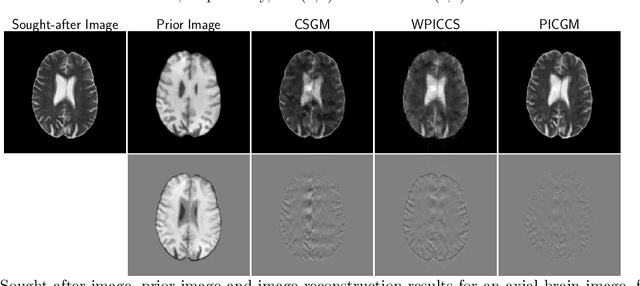

Abstract:Computed medical imaging systems require a computational reconstruction procedure for image formation. In order to recover a useful estimate of the object to-be-imaged when the recorded measurements are incomplete, prior knowledge about the nature of object must be utilized. In order to improve the conditioning of an ill-posed imaging inverse problem, deep learning approaches are being actively investigated for better representing object priors and constraints. This work proposes to use a style-based generative adversarial network (StyleGAN) to constrain an image reconstruction problem in the case where additional information in the form of a prior image of the sought-after object is available. An optimization problem is formulated in the intermediate latent-space of a StyleGAN, that is disentangled with respect to meaningful image attributes or "styles", such as the contrast used in magnetic resonance imaging (MRI). Discrepancy between the sought-after and prior images is measured in the disentangled latent-space, and is used to regularize the inverse problem in the form of constraints on specific styles of the disentangled latent-space. A stylized numerical study inspired by MR imaging is designed, where the sought-after and the prior image are structurally similar, but belong to different contrast mechanisms. The presented numerical studies demonstrate the superiority of the proposed approach as compared to classical approaches in the form of traditional metrics.

Abstract:Obtaining an accurate and reliable estimate of an object from highly incomplete imaging measurements remains a holy grail of imaging science. Deep learning methods have shown promise in learning object priors or constraints to improve the conditioning of an ill-posed imaging inverse problem. In this study, a framework for estimating an object of interest that is semantically related to a known prior image, is proposed. An optimization problem is formulated in the disentangled latent space of a style-based generative model, and semantically meaningful constraints are imposed using the disentangled latent representation of the prior image. Stable recovery from incomplete measurements with the help of a prior image is theoretically analyzed. Numerical experiments demonstrating the superior performance of our approach as compared to related methods are presented.